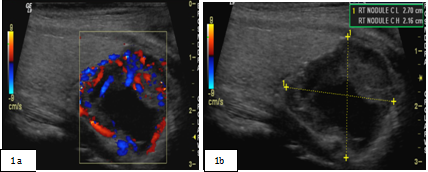

Neck ultrasound (Figure 1A & 1B) revealed a right dominant 2.8cm complex, solid and cystic nodule with intranodular and peripheral vascularity. She was admitted and was treated with intravenous (IV) normal saline. She received 1 dose of IV pamidronate 60mg. Her calcium level improved to 9.8mg/dl and was subsequently discharged. She underwent biopsy of the right thyroid nodule, which was consistent with parathyroid neoplasm possibly adenoma with immunohistochemistry negative for Thyroglobulin, TTF 1, Calcitonin and S 100. She was subsequently referred to endocrine surgery for evaluation of parathyriodectomy. CT scan of neck with 3D imaging reconstruction2 (Figure 2) study confirmed a large well defined nodule with peripheral enhancement suspicious for large right parathyroid adenoma. She underwent minimally invasive parathyriodectomy with fluid aspiration and intra-operative PTH levels fell from 289 pg/ml to 15.8 pg/ml. Pathology (Figure 3) was supportive of the diagnosis of atypical parathyroid adenoma with fragments of hyper cellular parathyroid neoplasm consisting of neoplastic cells with solid nest and trabecular growth patterns with focal capsular distortion and increased mitotic activity. Immunohistochemistry revealed Ki-67 proliferation index 1-3%, bcl-2 positive, diffuse strong and focal weak positive p 53. Post operatively; she was started on calcium and vitamin D supplementation. She is doing well and remains normocalcemic for 2 years following surgical resection with most recent calcium of 9.3mg/dl.

Figure 1A : Ultrasonographic findings consistent with right thyroid nodule with solid and cystic component.1B: prominent peripheral and intranodular vascularity.